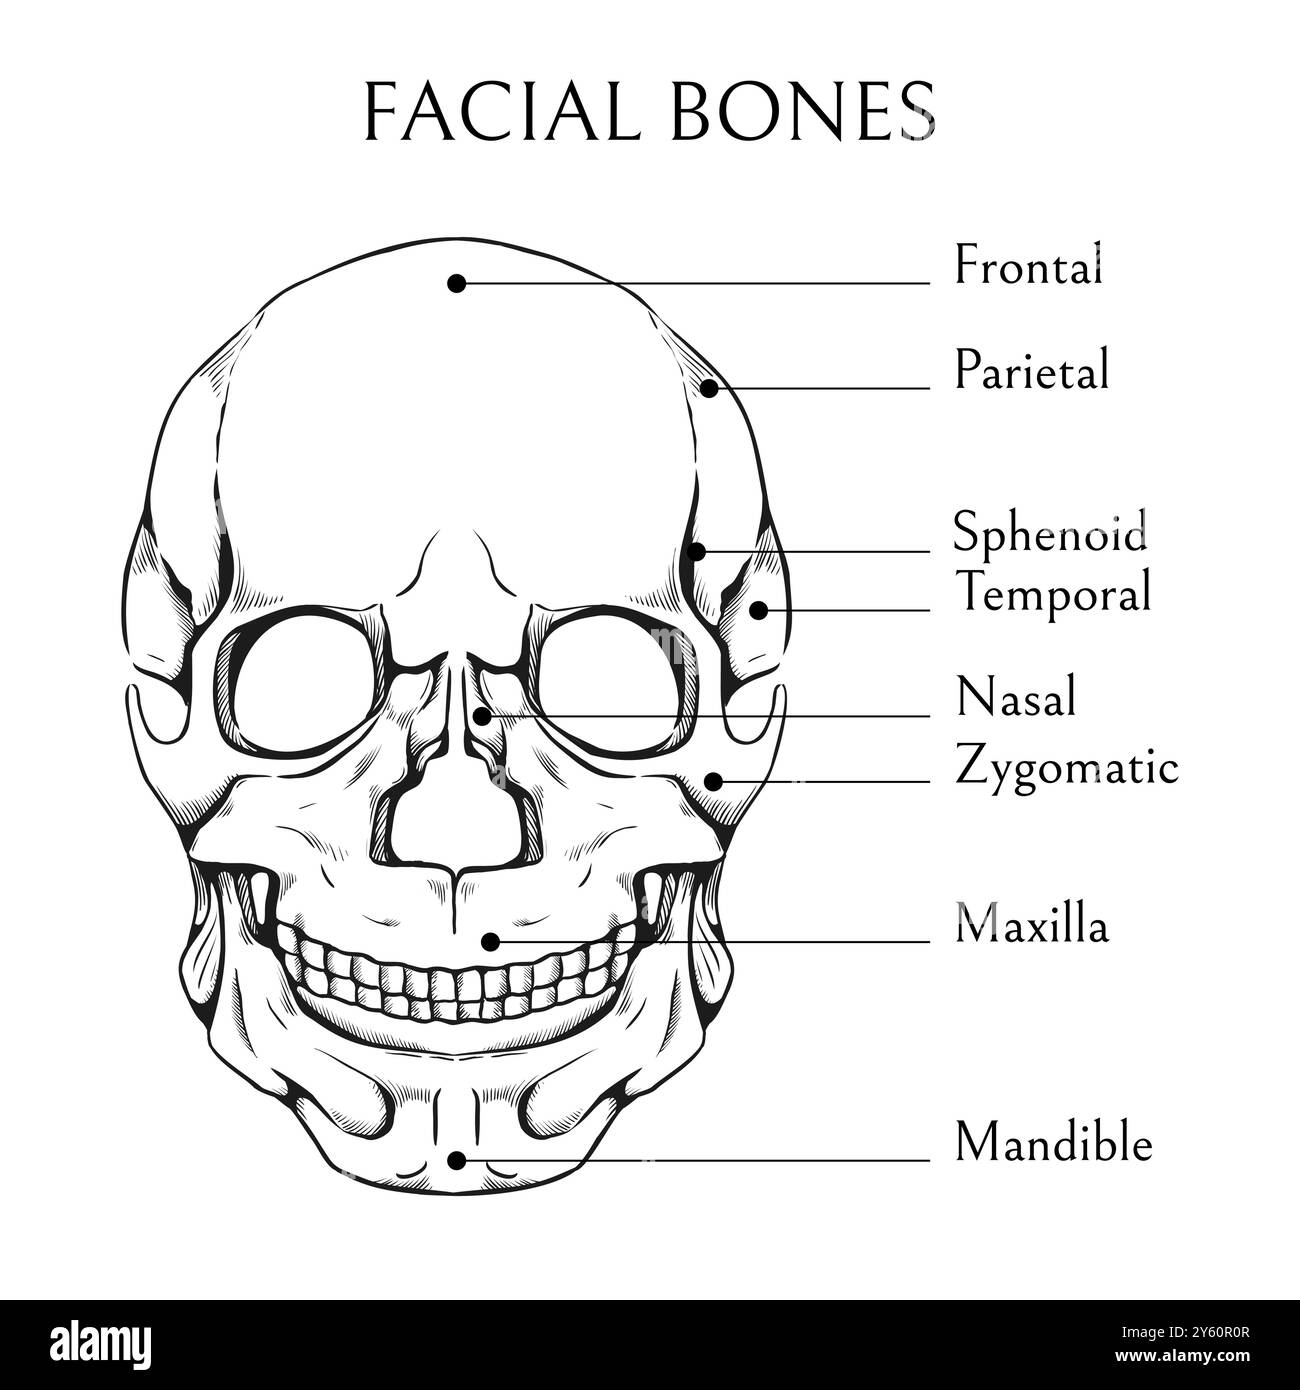

Hand drawn facial bones. Human skull sketch. Medical educational banner. Skeleton engraving diagram. Medicine science encyclopedia. Cranium skeletal structure. Inscription text. Vector anatomy poster Stock Vectorhttps://www.alamy.com/image-license-details/?v=1https://www.alamy.com/hand-drawn-facial-bones-human-skull-sketch-medical-educational-banner-skeleton-engraving-diagram-medicine-science-encyclopedia-cranium-skeletal-structure-inscription-text-vector-anatomy-poster-image623279239.html

Hand drawn facial bones. Human skull sketch. Medical educational banner. Skeleton engraving diagram. Medicine science encyclopedia. Cranium skeletal structure. Inscription text. Vector anatomy poster Stock Vectorhttps://www.alamy.com/image-license-details/?v=1https://www.alamy.com/hand-drawn-facial-bones-human-skull-sketch-medical-educational-banner-skeleton-engraving-diagram-medicine-science-encyclopedia-cranium-skeletal-structure-inscription-text-vector-anatomy-poster-image623279239.htmlRF2Y60R0R–Hand drawn facial bones. Human skull sketch. Medical educational banner. Skeleton engraving diagram. Medicine science encyclopedia. Cranium skeletal structure. Inscription text. Vector anatomy poster